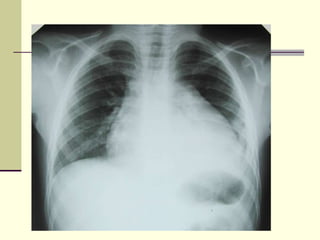

Рентгенография

Рентгенография грудной клетки

иногда выявляет расширение границ

сердца и/или признаки застоя в легких